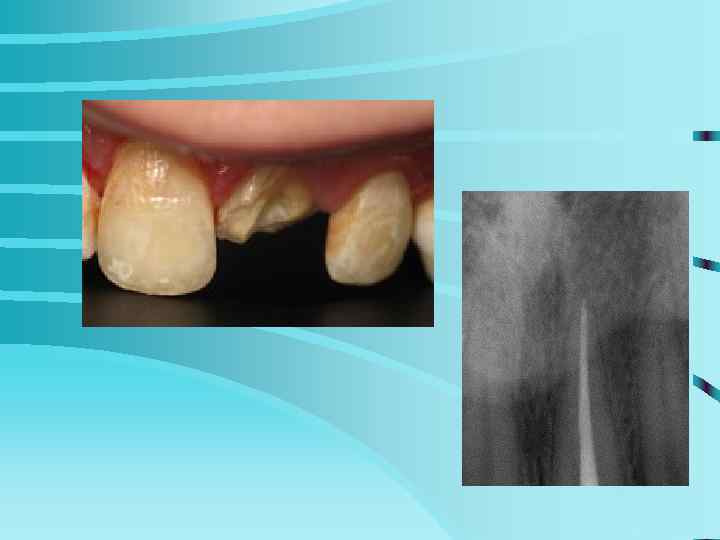

Том Круз устранил передний, потемневший депульпированный зуб, и отбелил всю линию.